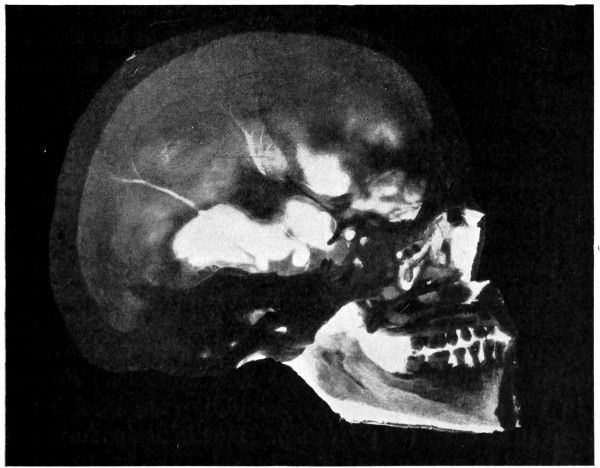

| 29 A and B. The base of the skull and the base as seen on transillumination | 70, 71 |

| 50 A and B. The inner aspect of the skull and the same seen on transillumination | 137 |